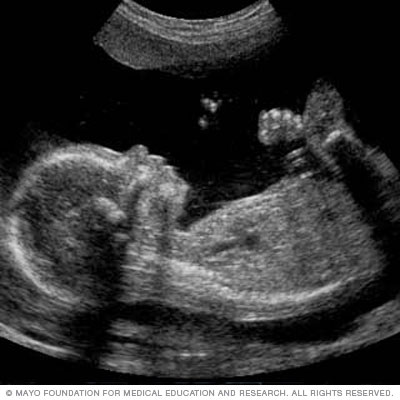

A congenital heart defect may be diagnosed during pregnancy or after birth. Signs of certain heart defects can be seen on a routine pregnancy ultrasound test (fetal ultrasound).

A life-threatening congenital heart defect is usually diagnosed soon after birth. Some may be discovered before birth during a pregnancy ultrasound.